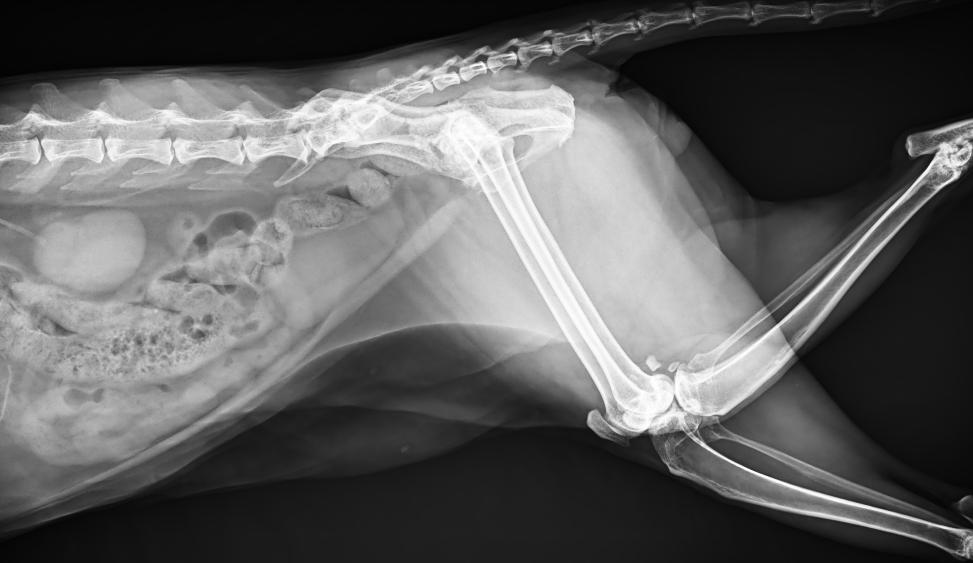

● 17*17大尺寸平板探測(cè)器,獲得高質(zhì)量圖像

● 優(yōu)異的空間分辨率及信噪比,提升圖像質(zhì)量

● 采用線噪聲消除技術(shù),使成像質(zhì)量提升40%

● 智能高效的圖像處理軟件,大幅提升圖像質(zhì)量